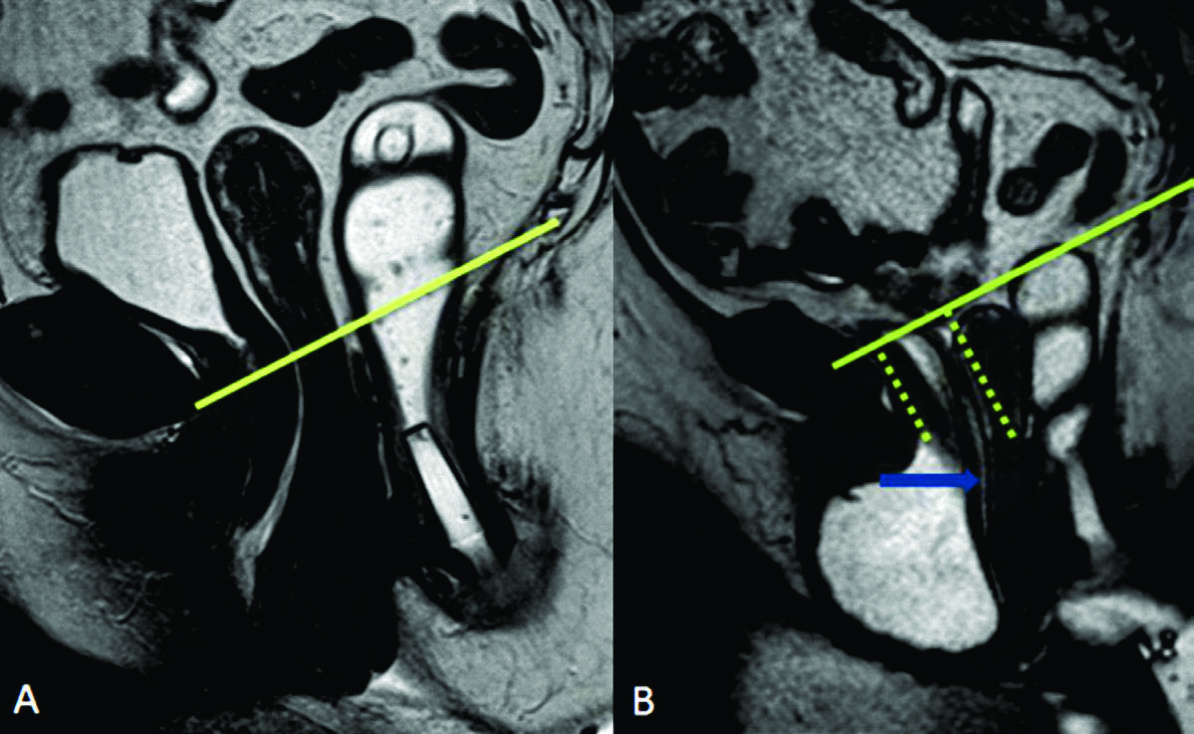

Figura 4

Línea H y línea M.Imágenes potenciadas en T2 de alta resolución en el plano sagital. Se observa el cambio en el valor que adopta la línea M y la línea H al comparar el reposo frente a la defecación. Según sus medidas en centímetros, se puede graduar en cuatro estadios diferentes.

La línea H se traza desde el borde inferior del pubis hasta la pared posterior del recto a la altura de la unión ano rectal, representando el diámetro anteroposterior del hiato urogenital, con un valor normal menor a 6 cm (Ver figuras 4).

La línea M es perpendicular a la PCL a nivel del sector más posterior de la línea H y representa el descenso del hiato del elevador, con un valor normal menor a 2 cm. El ángulo ano rectal es el ángulo entre el eje central del canal anal y la pared posterior del recto, con un valor normal entre 108º y 127º y una variación de hasta 15º en Valsalva.

Además se debe valorar la relajación del piso pélvico, a través del valor que adquiere tanto la línea H (apertura del hiato urogenital) como la línea M (descenso del piso pélvico) durante las maniobras dinámicas (Ver tabla 4) (7).